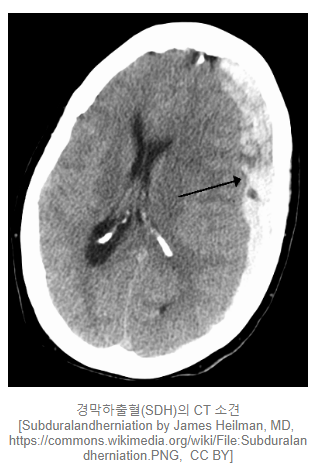

경막하출혈 (Subdural hemorrhage)

경막(Dura mater)과 지주막(Arachnoid mater) 사이에 발생. CT에서 오목한, 낫 모양으로 보입니다. 이 또한 외상에 의한 원인이 대부분이며, 위의 경막외출혈과는 반대로 정맥 손상에 의해 발생합니다.

동맥보다 압력이 낮은 정맥의 특성 상 경막하출혈이 경막외출혈(EDH)보다 출혈 양의 증가속도가 느려서 증상이 더 늦게 발생합니다. 그렇기 때문에 점차적으로 의식이 변화되고 소실되는 경우가 많습니다. 하지만, 머리의 손상이 심각하여 외상 자체의 충격이 크거나 출혈량이 많은 경우에는 즉각적인 의식 소실이 발생할 수 있습니다.

노인과 알코올 중독자 같이 뇌의 위축이 심한 환자에서는 그만큼 경막하 공간이 넓기 때문에 급성 경막하출혈이 발생할 위험도가 높습니다.

양이 적고 늘어나지 않을 경우에는 수술적 치료까지는 필요하지 않습니다. 하지만 양이 계속 늘어나고 뇌를 한 쪽으로 압박할 경우에는 수술적 치료가 필요합니다.